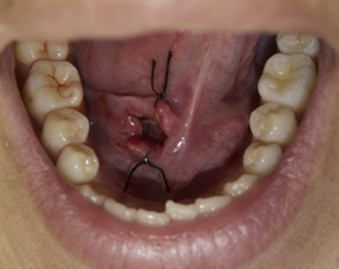

Treating a dentigerous cyst depends on its size. If it’s small, your dentist might be able to surgically remove it along with the affected tooth. In other cases, they might use a technique called marsupialization.

Marsupialization involves cutting open the cyst so it can drain. Once the fluid has drained, stitches are added to the edges of the incision to keep it open, which prevents another cyst from growing there.